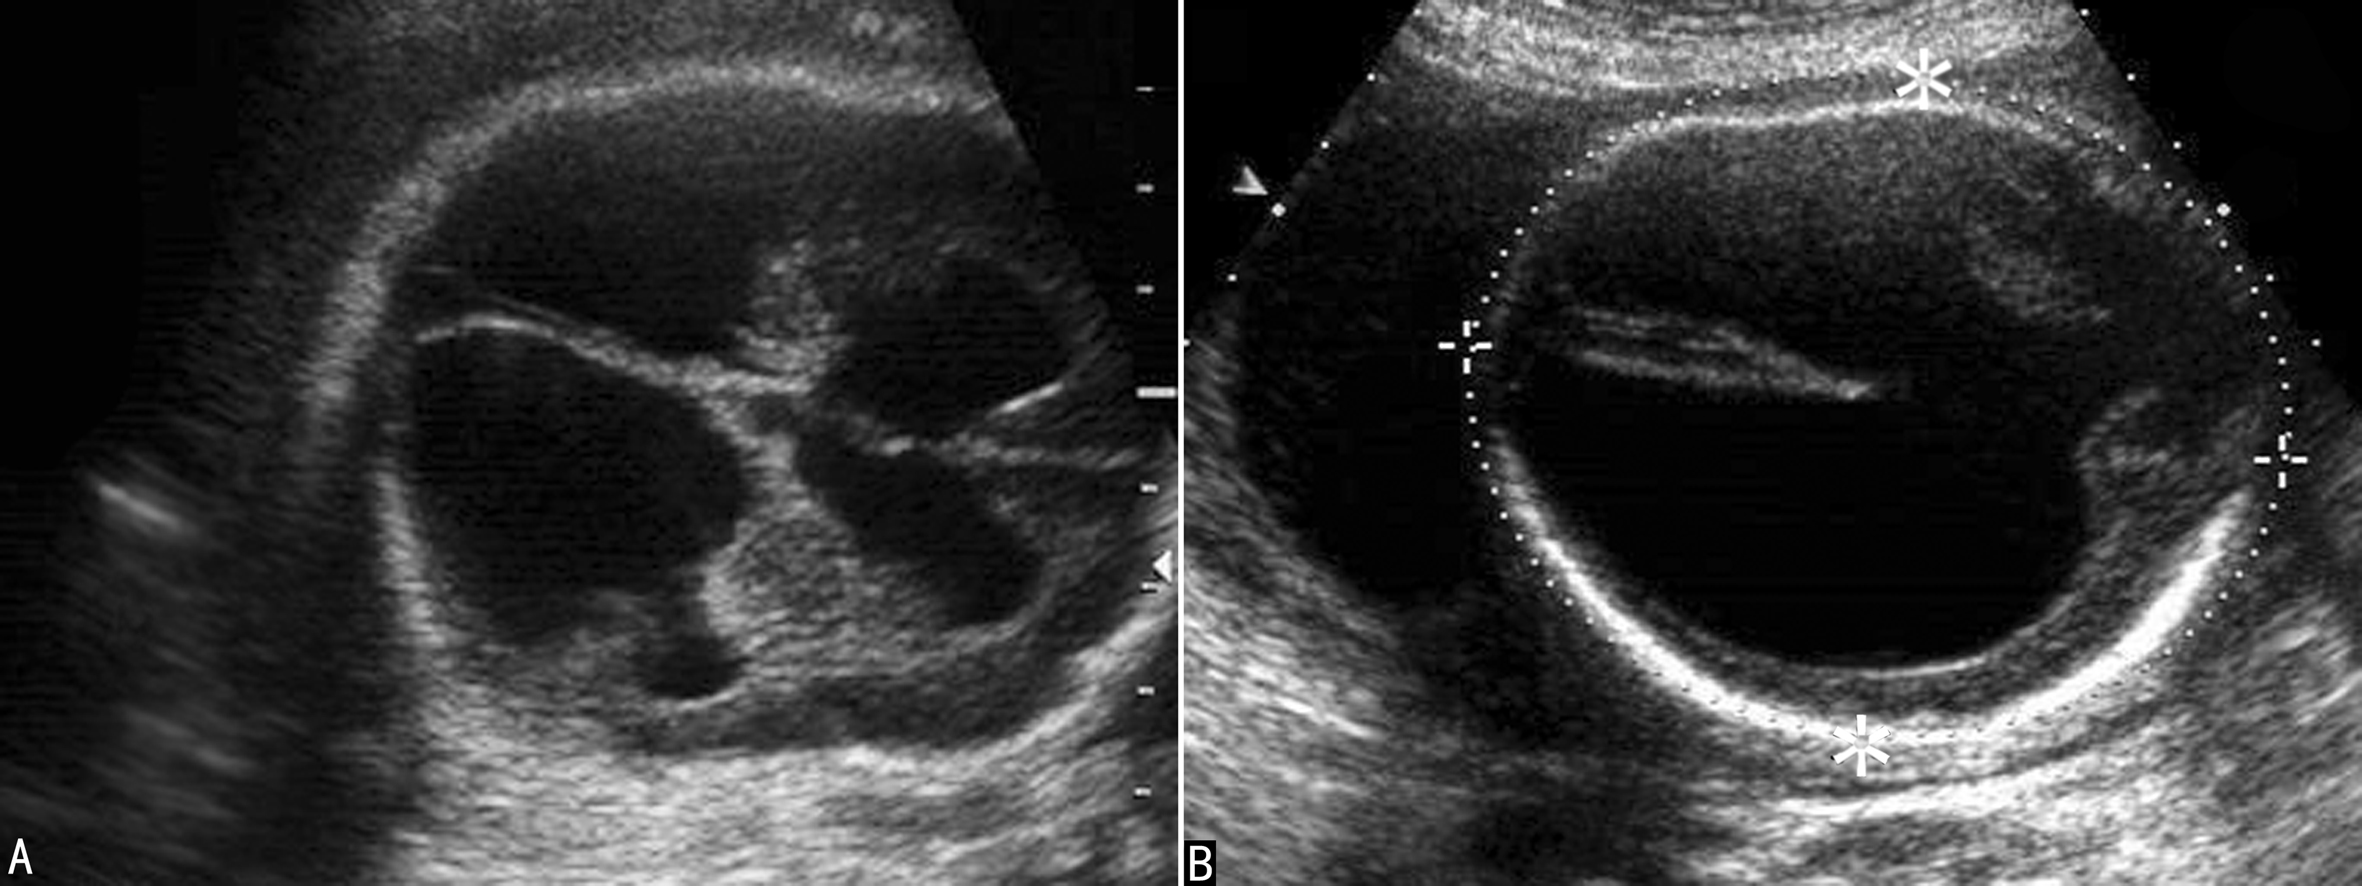

3.重度脑室增宽 重度侧脑室增宽(SVM)俗称HC(图3)。超声显像检查可以显示为对称性脑室扩张(图3,图4A),也可以显示为非对称性脑室扩张(图4B),严重时颅内完全由无回声的积液占据,脑组织显示不清。重度侧脑室增宽最常见的原因是中脑导水管硬化,并且有60%的胎儿伴有CNS结构异常,包括前脑无裂畸形、Dandy-Walker畸形、脊柱裂、小脑扁桃体下疝畸形、脑穿通畸形等,但较少合并染色体异常。超声显像检查显示胎儿头颅增大,脑室系统扩张,压力升高,脑室周围灰质、白质相继受压,严重时颅内结构不可辨认或显示不清,神经结构及功能严重受损,胎儿出生后多有严重的智力障碍。

图4胎儿重度脑积水声像图